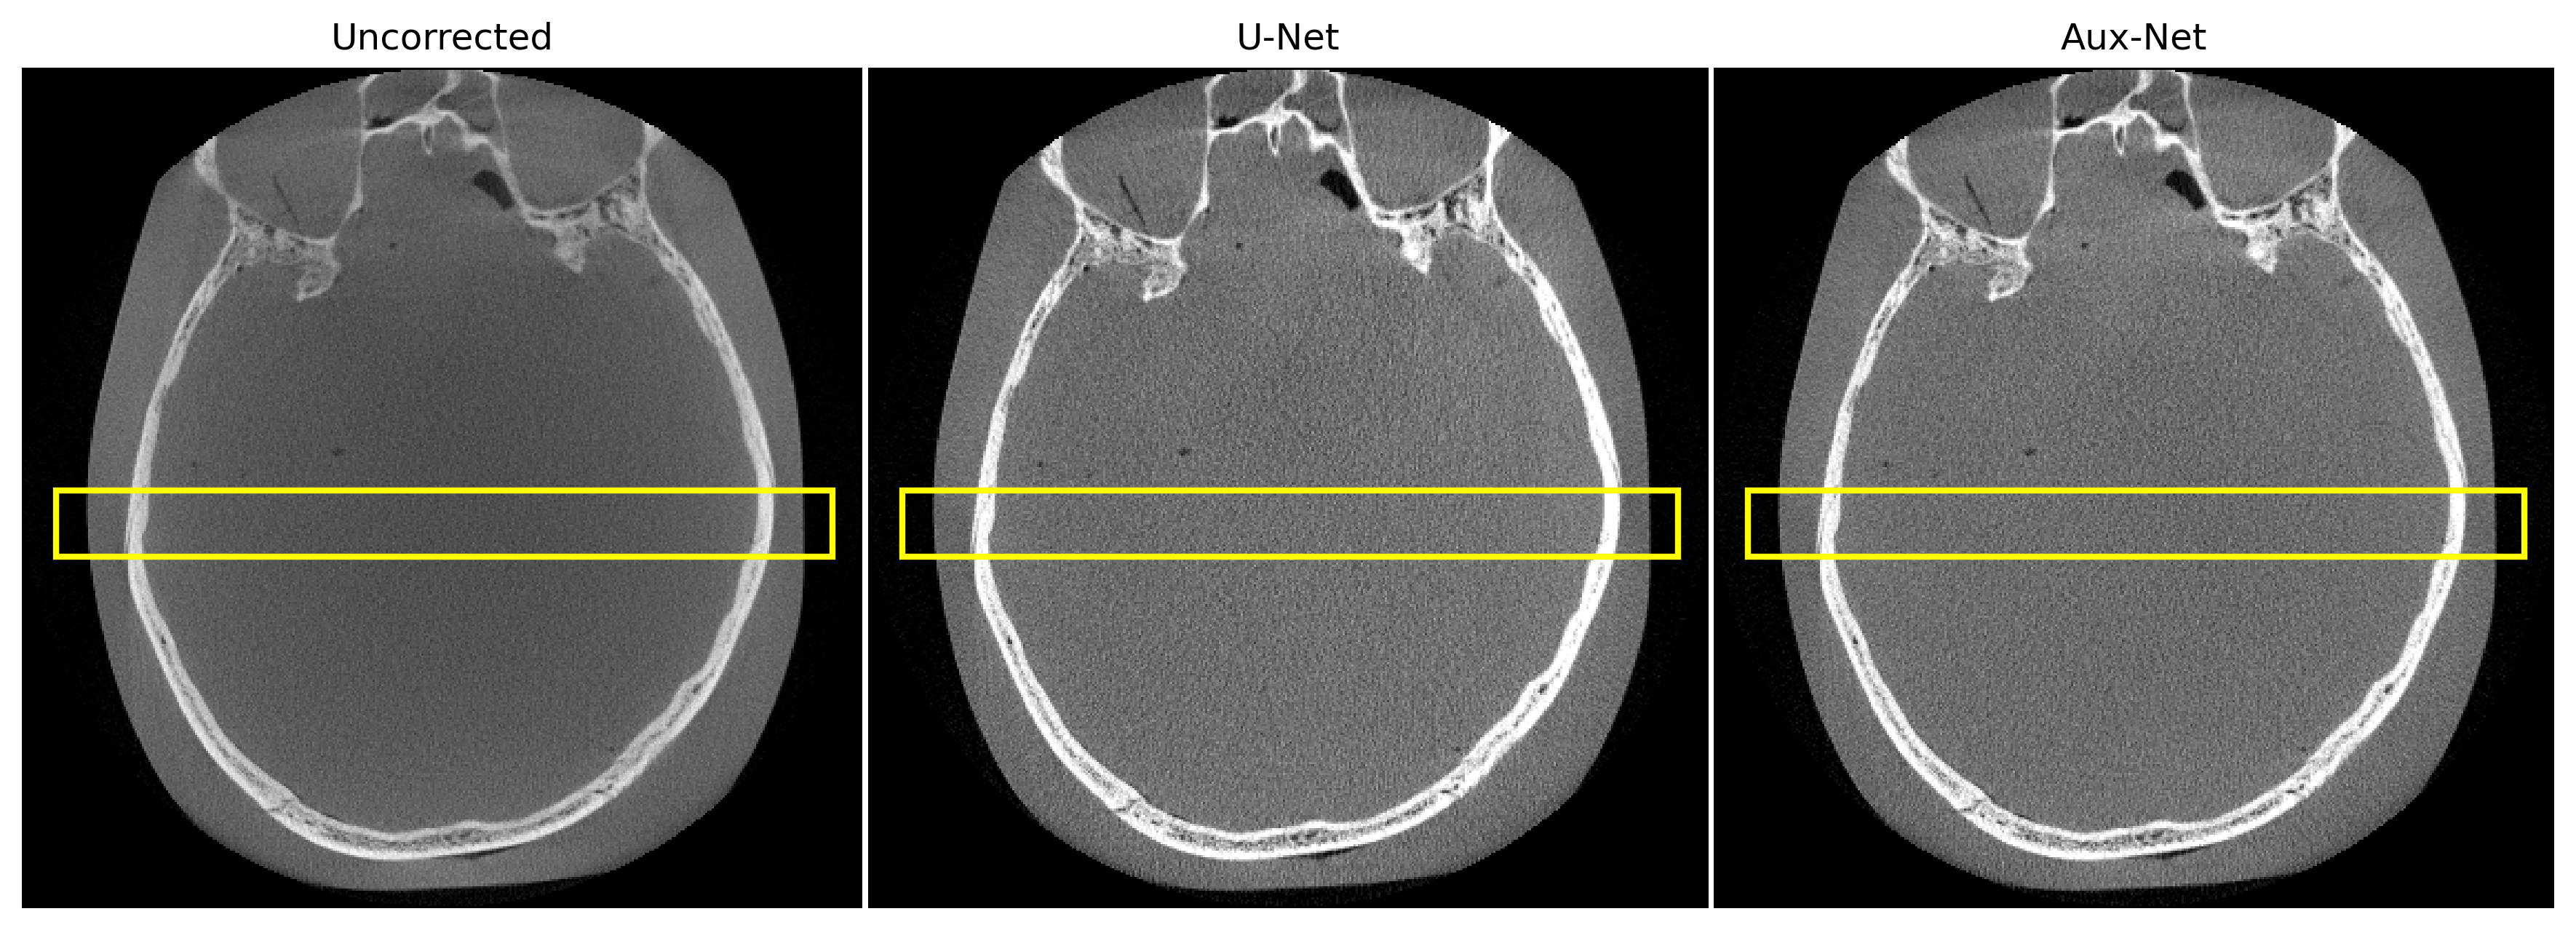

3.2 Scatter estimation on phantom scan

Figure 3 depicts the result of U-Net and Aux-Net based scatter corrected reconstructions for the two axial slices at different locations. The predicted scatter estimates were subtracted from the measurements and reconstruction was done using FDK algorithm for CBCT. The intensity profile is more stable for Aux-Net corrected image slices. Furthermore, the Aux-Net corrected reconstruction is more robust in the presence of high density object in comparison to the U-Net corrected reconstruction.